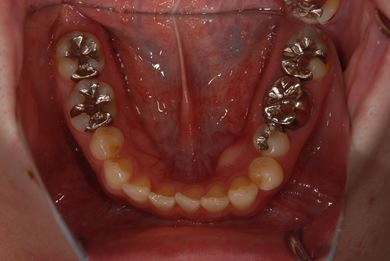

| 性別/年齢 | 女性 / 30歳 | ||||||||||||||||||||||||||||||||

| 主訴 | 上の奥歯を抜歯すべきかどうか、抜歯する場合はインプラント治療が可能かどうかの相談。 | ||||||||||||||||||||||||||||||||

| 治療方針 | ソケットリフトにて上顎洞を拳上し、インプラント治療を可能にする。 | ||||||||||||||||||||||||||||||||

| 治療内容 | インプラント2本(ソケットリフト)、メタルボンドセラミッククラウン1本 | ||||||||||||||||||||||||||||||||